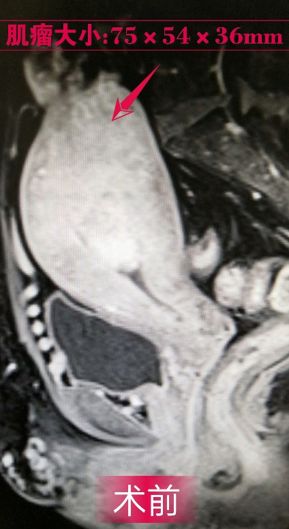

48岁,因“月经紊乱伴经量增多3年,阴道出血17天”入院,诊断为:子宫肌瘤。治疗后第一天,阴道出血停止,治疗后3个月,月经周期恢复规律,血红蛋白在正常范围,6个月复查磁共振显示子宫肌瘤已坏死、吸收、缩小。